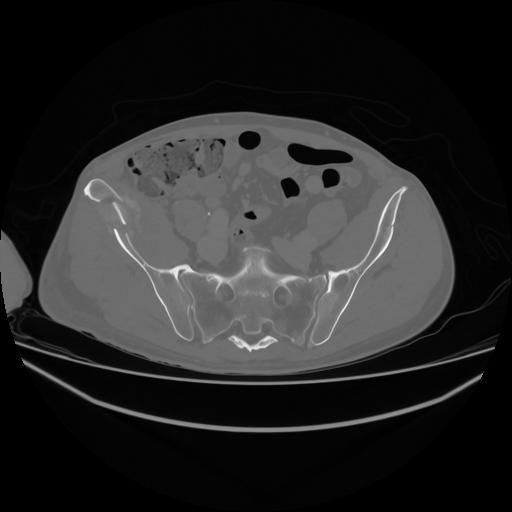

5 CUERPO,CE,Vol,1.0,CUERPO,,